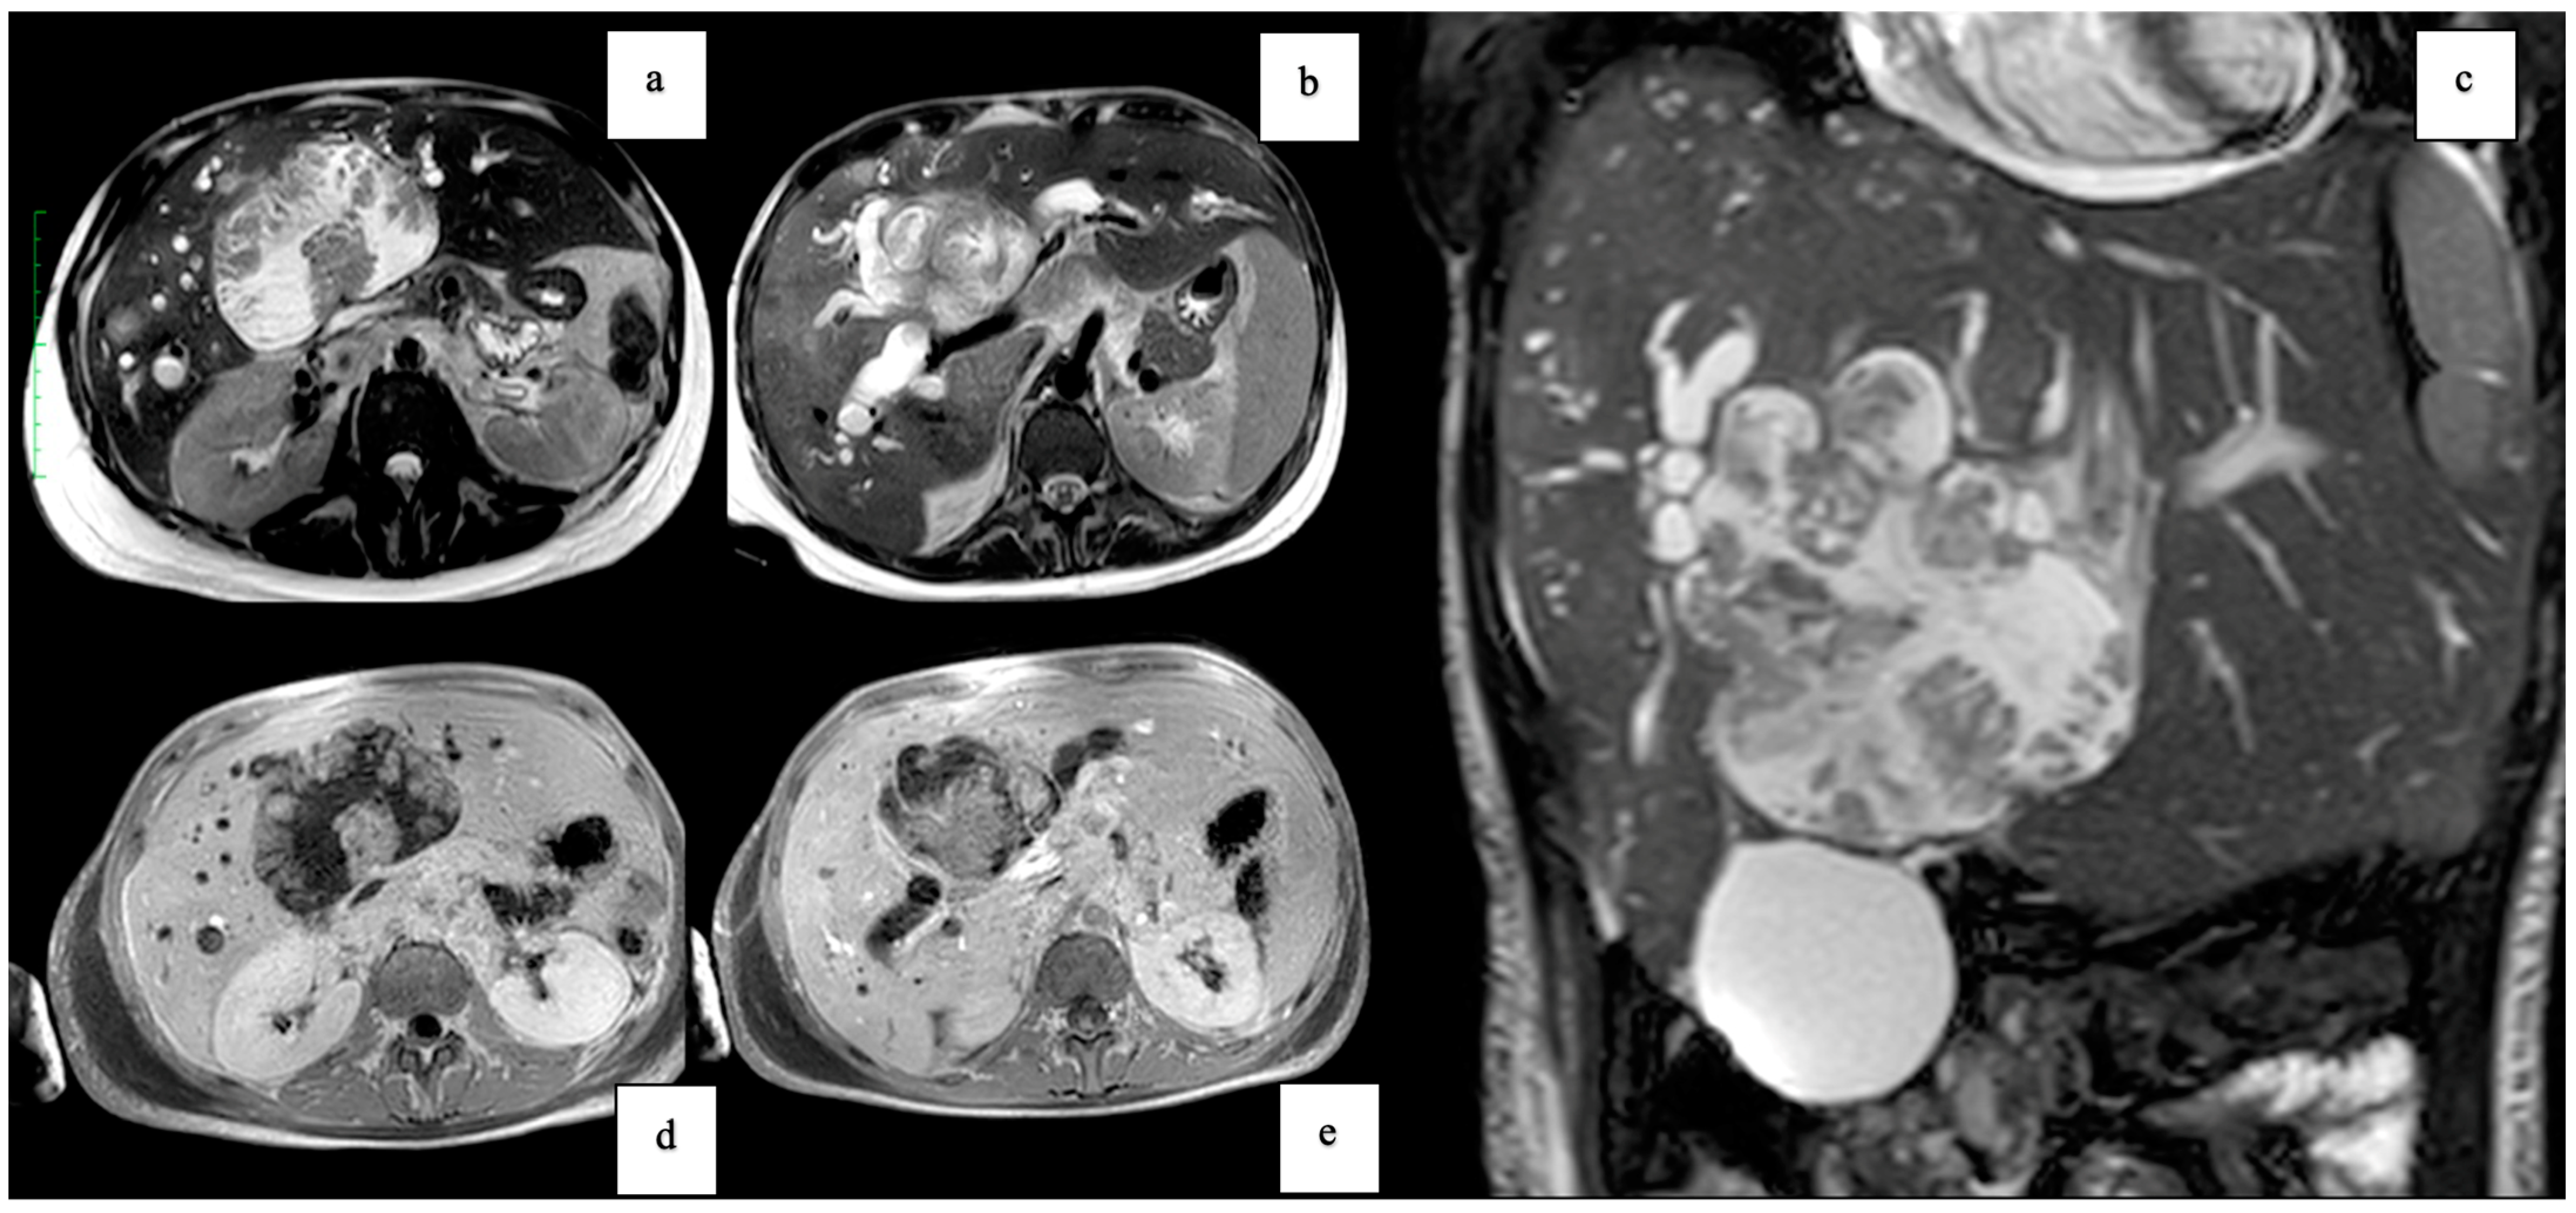

3. Case Report 2

| Tumor Characteristics | Large cystic mass, thin walls, internal septa, papillary projections, enhancing solid components | Large lesion in left hepatic lobe, hyperintensity in T2-weighted images, restricted diffusion, contrast enhancement |

| Surgical Findings | Partially exophytic floating soft mass | Extensive intrahepatic metastases, vascular involvement |

| Histopathological Findings | IPNB with foci of adenocarcinoma, oncocytic appearance, varying degrees of dysplasia, mucus within cyst | Adenocarcinoma with papillary clear cell and mucinous appearance, gland ectasis, cystic or pseudocystic aspects |